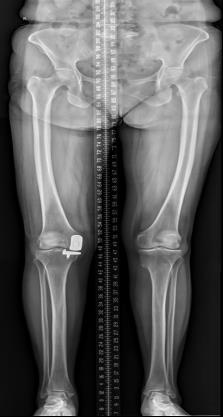

该科擅长对膝关节严重创伤(包括股骨远端骨折、髌骨骨折、胫骨平台骨折等)、膝骨关节炎阶梯化治疗、保膝治疗、膝关节微创单髁置换术、全膝关节置换术、膝关节翻修术具有丰富的临床诊疗经验,追求微创、无痛、快速康复。

对膝关节骨性关节炎采取阶梯化治疗方案,坚持中西并重、内外兼治的原则,取得满意的治疗效果。早期利用中医中药的传统优势,使用中医外治法,例如烫熨治疗、中药涂擦、雷火灸、中药塌渍等,同时辩证内服本院中药制剂及内服方药以及配合西药治疗,开展健康教育,运用运动疗法、物理治疗等辅助支持;中期开展软骨修复、截骨术、单髁置换术、髌股关节置换术等;对于终末期的膝关节OA采用全膝关节置换术。